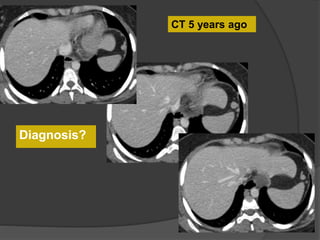

CT 5 years ago

Diagnosis?

CT 5 years agoCurrent CT

Case 1 Diagnosis: Infarcted splenule

Infarcted splenule

 Accessory spleen (splenule ) : failure of fusion of the splenic

anlage, seen in up to 30% of autopsies

 Occur on vascular pedicles and thus at risk for torsion

 Differentiate from polysplenia and splenosis. Identify an intact

spleen, no other splenic foci and normal situs

 Recognize this entity as a cause of abdominal pain that can be

managed non-surgically

Case 14 Diagnosis: Infarcted splenule